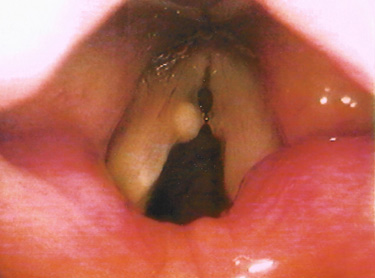

성대낭종은 선천성과 이차적인 후천성에 의해 발생하며 성대결절과 같이 음성을 과도하게 사용한 경우 자주 나타납니다.

후두미세수술을 시행하며 성대점막의 유착과 강직을 방지하기 위해 PDL레이저 성대수술을 병행하여 시행하기도 합니다.

성대낭종의 수술은 낭종의 주머니까지 모두 제거하는 것이 재발률을 줄일 수 있습니다.